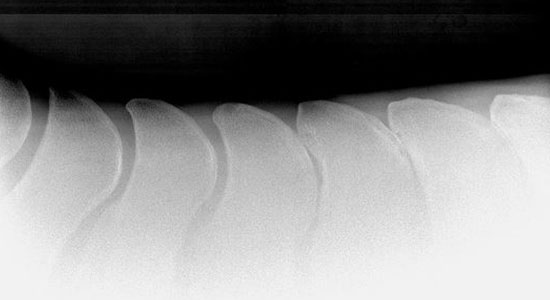

Im Zentrum der Chiropraktik steht die Beseitigung bzw. Lösung einer gestörten Funktion der Wirbelsäule und die Auswirkungen dieser Störungen auf das Nervensystem und den Gesamtorganismus.